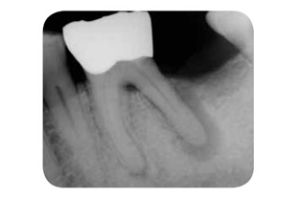

2.根管側支(圖1,2):即牙根側壁上的交通支,在近根尖1/3處最多,故深牙周袋達根尖1/3處時,牙髓受影響的機會就大大增加。

根管治療後,有些牙可能發生牙根縱裂。牙根縱裂也有不少發生在活髓牙。臨床表現為患牙有鈍痛、咬物痛、局限的深牙周袋,活髓牙的根縱裂還可見到典型的根管影像增寬(圖5),還可以反覆發生牙周膿腫,出現竇道。